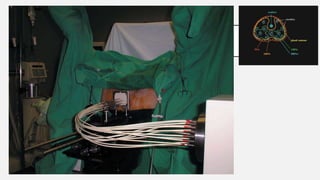

BRAQUITERAPIA

Manoharan SR, Rodriguez RR, Bobba VS,

Chandrashekar M - J Med Phys (2010)

ASSOCIADO À CIRURGIA

http://www.praticahospitalar.com.br/pratica%2037/paginas/materia%2014-37.htm